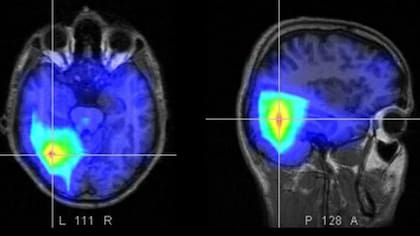

NUEVA YORK.- Aunque las encuestas muestran que la mayoría de los norteamericanos consideran que la marihuana es inofensiva, las nuevas investigaciones publicadas esta semana en la revista científica Heart revelan que el consumo de esa droga está asociado a un mayor riesgo de infarto y un accidente cerebro vascular (ACV), incluso entre los jóvenes.

La investigación analizó los datos de 24 estudios previos y también descubrió que el consumo de marihuana está asociado con un doble de riesgo de muerte por un problema cardiovascular. Si bien esos datos solo muestran una correlación y no prueban que la marihuana sea la causante de esos efectos, lo que sí ya está muy demostrado es que la droga eleva la presión arterial y las pulsaciones y puede alterar el ritmo cardíaco, según la doctora Ersilia DeFilippis, cardióloga del Centro Médico Irving de la Universidad de Columbia. Y hay varios otros estudios que también sugieren la misma relación entre la droga y los problemas cardiovasculares.